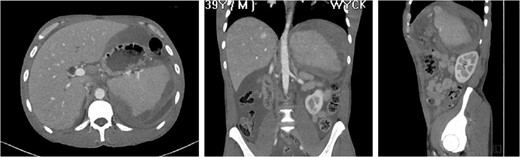

3D reconstruction and coronal CT after placement of pigtail drainage catheter.

A study conducted over an 11-year period reports that minor complications of fever, left-sided pleural effusions, and coil migration occur in 34% of patients while major complications of splenic abscess, infarction, cyst, and contrast induced renal insufficiency occur in 14% of patients who undergo TSAE. Of the patients in the study, ¾ of patients with major complications had undergone distal embolization, defined as distal to the main splenic artery trunk [7]. During the post-procedure course, our patient was noted to have minor complications of fever and left-sided pleural effusion as well as a major complication of intra-abdominal abscess.

Our patient was vaccinated given that post-procedure CT showed the spleen to be partially necrotic with only two islands of well-perfused, preserved spleen depicting >15% decrease in splenic volume. The plan was to perform interval splenectomy however he was lost to follow up.